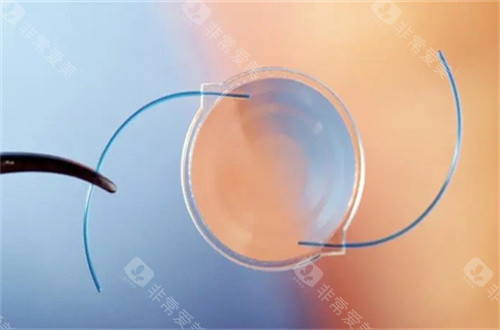

三焦点晶体:相比传统单焦点,可同时优化远、中、近视力,术后不用戴老花镜。

个性化方案:根据患者角膜状况、用眼习惯定制手术,比如喜欢看书或开车的老人,医生会调整晶体参数优化视觉结果。

普瑞眼科在济南的口碑一直不错,尤其是其引进的德国蔡司三焦点晶体技术,能帮助老年人一次性解决白内障和老花眼问题。